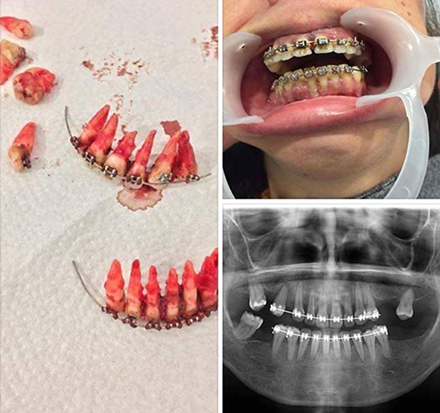

เผยภาพฟันร่วงหมดปากในโลกโซเชียล ใช้รณรงค์ในฟิลิปปินส์อย่าจัดฟันเถื่อน

อุปนายกสมาคมทันตแพทย์จัดฟันแห่งประเทศไทยเผยภาพจัดฟันจนฟันร่วงหมดปากในโลกโซเชียล เป็นภาพที่ใช้รณรงค์ไม่ให้ประชาชนไปจัดฟันเถื่อนในฟิลิปปินส์ ย้ำวัยรุ่นอย่าเอาวัสดุมาติดบนฟันตัวเอง อาจทำให้ฟันเสียรูปหรือฟันผุจนต้องถอนทิ้ง

ทพญ.เรืองรัตน์ โกมลภิส อุปนายกสมาคมทันตแพทย์จัดฟันแห่งประเทศไทย เปิดเผยว่า กรณีภาพฟันที่ติดอยู่กับเส้นลวดคล้ายอุปกรณ์จัดฟันถูกถอนออกมาทั้งยวงซึ่งมีการแชร์กันในโลกโซเชียลนั้น จากการตรวจสอบพบว่าเป็นภาพที่แชร์มาจากแพทย์ในฟิลิปปินส์และทางสมาคมทันตแพทย์จัดฟันฯ ได้ติดต่อสอบถามรายละเอียดไปก็ได้รับคำตอบว่าเป็นภาพที่ใช้เพื่อรณรงค์ไม่ให้ประชาชนไปจัดฟันเองหรือจัดฟันเถื่อน แต่ต้นตอของภาพไม่ทราบว่าเป็นภาพของใคร และไม่ทราบว่าการที่ฟันถูกถอนออกมาทั้งยวงแบบนี้เกิดจากการจัดฟันหรือถูกถอนด้วยสาเหตุอื่น เนื่องจากหากพิจารณาภาพนี้อย่างละเอียดจะพบว่ามีโรคปริทันต์ร่วมด้วย

หมายเหตุ : ภาพประกอบจาก Eduardo O.Ricio